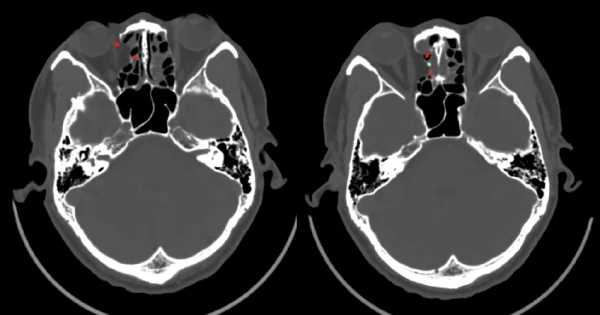

眼眶骨折是指眼眶内壁或外壁的骨骼受到外力冲击后发生骨折。这种骨折类型复杂且多样,不仅会影响视力,还可能对面部其它结构造成损伤。通过了解眼眶骨折的原因、危害及其预防和治疗方法,我们能够更好地保护自己和家人。

眼眶骨折按照受伤部位和骨折类型可以分为不同类型。最常见的类型包括下壁骨折和内壁骨折,其他少见类型如外壁骨折和上壁骨折。眼眶骨折可能导致多种并发症,例如眼球移位、复视、眼球运动障碍、视力下降等。严重的眼眶骨折还可能伴随颅脑损伤,导致永久性视力损失,甚至危及生命。

眼眶骨折造成的直接影响是眼球移位或塌陷,这不仅会导致外观上显著的改变,还会产生复视症状,即患者看到的物体出现重影,这会大大影响日常生活和工作。此外,下壁骨折可能导致眼球垂直运动受限,内壁骨折可能引发严重的感染和眼窝气肿。